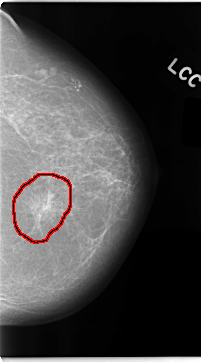

C_0047_1.LEFT_CC

LEFT_CC LINES 4696 PIXELS_PER_LINE 2608 BITS_PER_PIXEL 12 RESOLUTION 50 OVERLAY

FILE: C_0047_1.LEFT_CC.OVERLAY

TOTAL_ABNORMALITIES 1

ABNORMALITY 1

LESION_TYPE CALCIFICATION TYPE AMORPHOUS DISTRIBUTION CLUSTERED

LESION_TYPE MASS SHAPE ARCHITECTURAL_DISTORTION MARGINS N/A

ASSESSMENT 5

SUBTLETY 5

PATHOLOGY MALIGNANT

TOTAL_OUTLINES 1

BOUNDARY